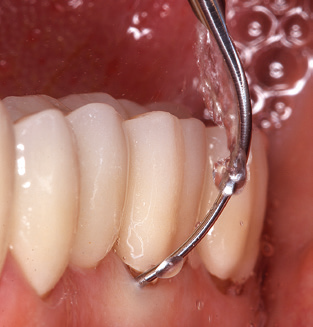

Good illumination of the working field facilitates the process considerably. The system used by the authors achieves this thanks to a 5x LED ring integrated in the handpiece. Naturally, a range of working tips for different indications is also offered. A straight, universally employable tip is the basic instrument required for machine cleaning of natural teeth (Fig. 5a and b). Curved tips, which allow access to exposed furcations, are also available for hard-to-reach areas in the posterior region (Fig. 6).